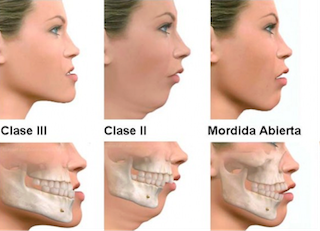

■骨格性(Skeletal Class III)

・上顎の成長不足(劣成長)または下顎の過成長により、上下の骨格バランスが崩れる

・遺伝的要素が強いが、環境要因(呼吸、舌癖)でも助長される

・特に思春期以降に下顎が急成長する「後出し型」も多い

■ 歯槽性(Dental Class III)

・骨格は正常だが、下の前歯が前方に傾斜していて噛み合わせが逆になっている

・乳歯期や学童期の咬み合わせの乱れを放置した結果起きる

下の顎が前に出ている場合、俗的には、「しゃくれ顔」や「受け口」、「あごが長い」、などと言うこともあります。矯正歯科診断学では、「反対咬合」、「下顎前突」と言われています。

反対咬合とは、俗に“うけ口”といわれるように、下の前歯が上の前歯より前方にでてしまっている状態をいいます。 これは、噛み癖によるもの、歯の位置や傾きの異常によって起こっているもの、顔のあごの骨の上顎骨または下顎骨の位置異常や大きさの不調和によって起こっているものがあります。

成長期に下顎前突が認められる場合、正常な顎骨の成長を阻害し、いま以上にその状態が悪くなる可能性があります。 そのため下顎前突の程度がより悪化し、その状態を改善するには、健全な歯の抜歯を併用しなければ治すことができなくなる可能性が高まります。また、その状態が極めて重度の場合、手術を併用して骨の位置から改善しなければならないこともあります。

2.あごの発育が悪いが、成長が残っていない場合(身長がほぼ伸び切ってしまっている方)

あごのバランスを良好に誘導するということは出来ませんので、今の骨格のまま歯を移動して受け口を改善します。骨格性の不正が強い場合、顎変形症と呼ばれあごの骨を外科的に修正する方もいます。